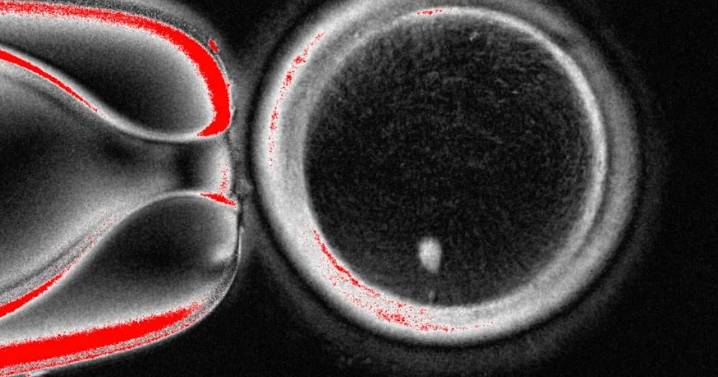

WASHINGTON (AP) — Oregon scientists used human skin cells to create fertilizable eggs, a step in the quest to develop lab-grown eggs or sperm to one day help people conceive.

But the experiment resulted in abnormalities in the chromosomes, prompting the Oregon Health & Science University team to caution it could take a decade of additional research before such a technique might be ready for trials in people.